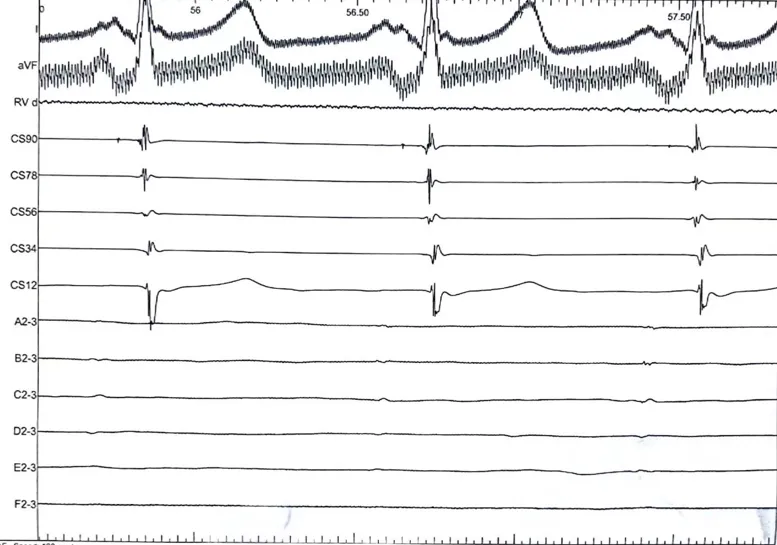

LSPV消融

消融导管呈网篮与花瓣形态下放电。

LSPV,消融前后电位。消融后电位即刻消失。

LIPV,消融前后电位。消融后电位即刻消失。

RSPV消融

RSPV,消融前后电位。消融后电位即刻消失。

RIPV消融

RIPV,消融前后电位。消融后电位即刻消失。

消融后电位验证

消融完成后,使用三维进行基质标测,验证肺静脉隔离符合消融终点。X线透视确认心包正常。手术顺利结束,患者安返病房。